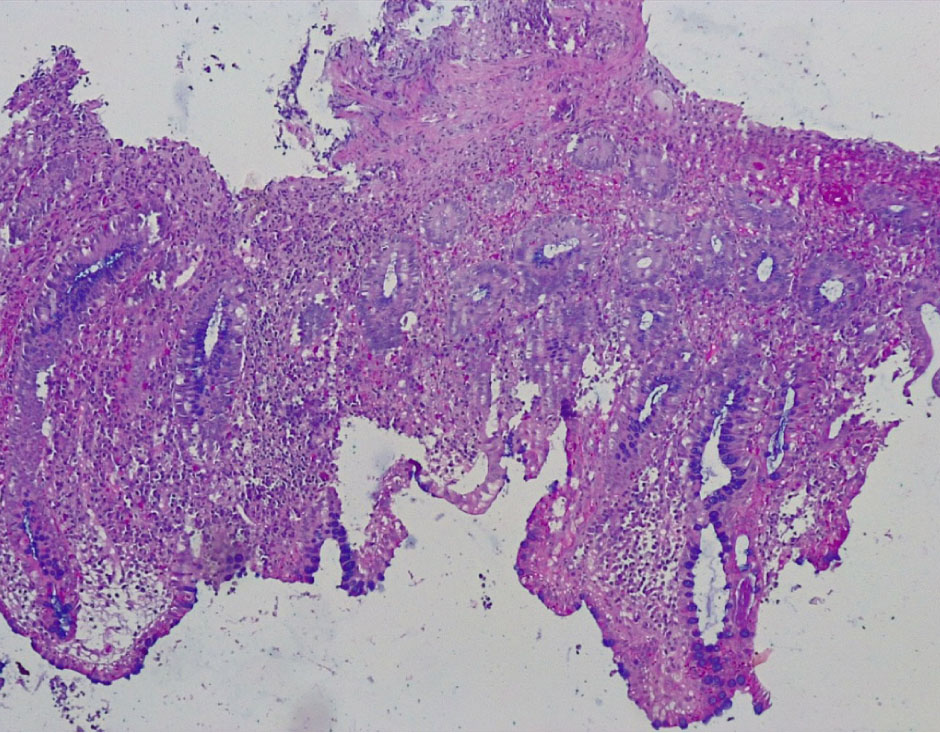

В контрольной группе биопсий слизистой оболочки (СО) толстой кишки, выполненной по поводу хронического поверхностного колита, были обнаружены следующие морфо-гистохимические изменения. СО толстой кишки была сохранена, цилиндрический (столбчатый) эпителий располагался в один слой, содержал на всем протяжении кислые гликопротеиды (ШИК-реакция). Крипты СО на всем протяжении были сформированы правильно, содержали до 12–15 бокаловидных клеток на крипту, содержали альциан+ муцин, что свидетельствовало о наличии в них нейтральных мукополисахаридов (рис. 1, 2).

Рис. 1. Контрольная группа: нормальное строение слизистой оболочки толстой кишки с сохранением цилиндрического эпителия и крипт, содержащих бокаловидные клетки. Окр. гематоксилин-эозином, ×100

Рис. 2. Контрольная группа: на поверхности слизистой оболочки толстой кишки цилиндрический эпителий сохранен, содержит кислые гликопротеиды. Бокаловидные клетки представлены во всех криптах, содержат альциан + мукополисахариды. ШИК-реакция с докраской альциановым синим, ×100